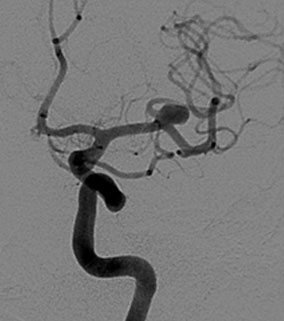

Aneurismas cerebrales:

Son dilataciones vasculares localizadas en arterias cerebrales que pueden ocasionar síntomas por ruptura (causando un hemorragia intracraneana brusca, enfermedad asociada a alto riesgo de vida o secuelas); por compresión de estructuras adyacentes. Raramente pueden ser fuente de embolos que ocluyen arterias más pequeñas y distantes.

Embolización de aneurismas cerebrales

El objetivo del tratamiento de los aneurismas cerebrales es excluirlos de la circulación normal para bloquear el ingreso de sangre a su interior evitando así su ruptura, o reduciendo el efecto de masa pulsátil sobre estructuras adyacentes.

La neurocirugía endovascular puede realizar este tratamiento mediante la embolización (oclusión) del saco aneurismático con espirales desprendibles (coils) o mediante la reconstrucción del vaso portador mediante la colocación de stent o dispositivos diversores de flujo. Algunos aneurismas requieren de la combinación de ambas técnicas.